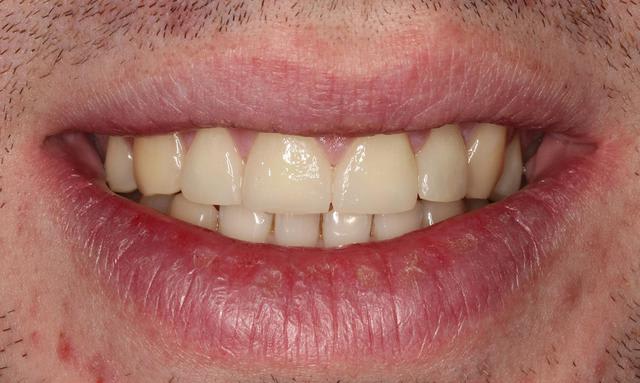

6 sourire final, 6 jours après la pose des définitives (des E max).

le patient est très content, et moi aussi!